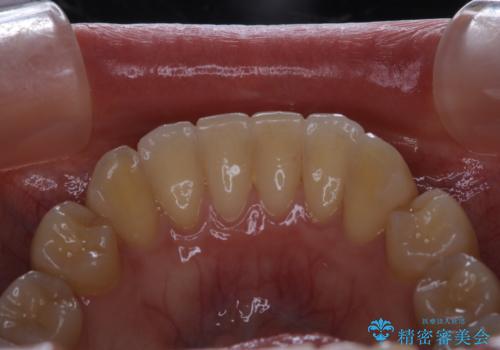

- インビザラインでのマウスピース矯正が終了したため、きれいにクリーニングして口元を明るい印象にしたいとのことでした。PMTC60分コースを行いました。

矯正治療が終わり、せっかくきれいになった歯並びも、虫歯・歯周病などになってしまっては元も子もありません。

矯正治療やセラミックなどによる被せ物の治療終了のタイミングではクリーニングを行い、汚れや着色の除去、歯と歯の間・歯と歯肉との境目などのケアをしっかりすることをおすすめしています。

ご自身での歯ブラシ・セルフケアを行うと同時に、定期的なクリーニング(PMTC)を行うことで、いつまでも健康な歯を保つことができます。